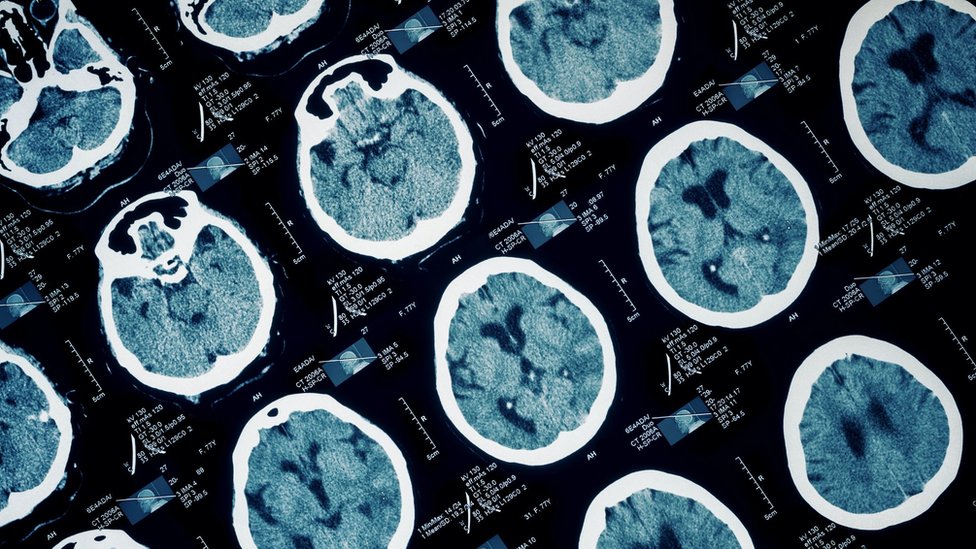

Između 40 i 60 odsto osuđenih zločinaca ima povrede mozga ili ozbiljne bolesti koje utiču na njihovo ponašanje, pa stručnjaci navode da postoji bojazan da ponovo počine zločin kada izađu iz zatvora.